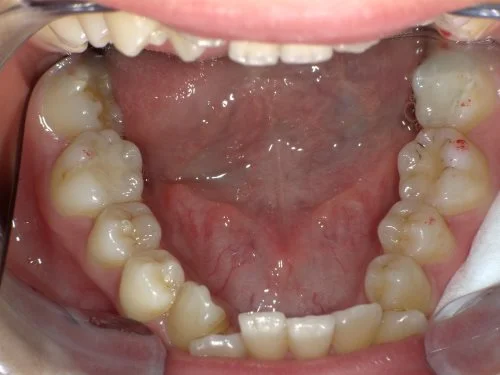

<症例7>歯がガタガタで噛み合わせが悪くお悩み

抜歯無し・マウスピースのみで矯正した症例です。

もともと歯列弓が非常に狭く、V字に近い形をしていたので噛み合わせも非常に不安定でした。

また、下顎前歯部がかなり上の方に生えていたため、下の前歯が上の前歯を突き上げてしまい出っ歯の状態になっていました。

現在では見た目はもちろん、臼歯の噛み合わせも改善しております。

患者様と症状

主訴:歯のガタガタ、噛み合わせが悪い

性別・年齢:20代女性

問題点:叢生(重度)、V字歯列弓、ディープバイト

診断:前歯部の叢生を伴うアングルⅠ級、骨格性Ⅰ級の不正咬合

主なリスク:臼歯の移動に伴い一時的に咬合しにくくなる、歯肉退縮

症状:叢生(そうせい) 過蓋咬合(かがいこうごう)

治療内容

治療期間:1年10ヶ月

治療費用:990,000円(税込)

プラン:Full2プラン

抜歯:無し

再診治療費:無し

追加治療費:無し

保定装置費:無し

治療前後の写真